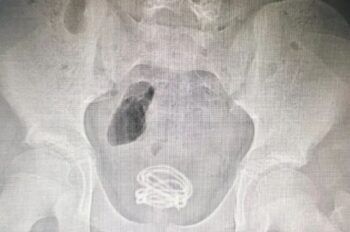

Un adolescente de 13 años, identificado como Xiao He, debió recibir atención en el hospital de Dongguan, China, pues intentó saber de dónde provenía la orina y se introdujo 70 centímetros de cable en el pene. Según medios locales, el jovencito se obsesionó con el varias semanas antes, y en lugar de buscar información en […]